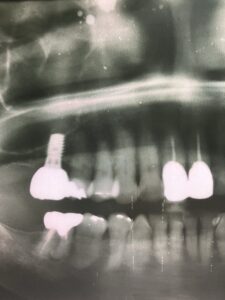

インプラントの上部構造の最終補綴物にメタルボンドと呼ばれるセラミックが使用されていました。今でも使用しますが1番の欠点として破折の可能性があることです。近年、物性や神秘性が格段に向上したジルコニアが、第一選択上がるようになりました。

フルジルコニアクラウンは、歯科補綴の一種で、全てジルコニアというセラミック素材でできた被せ物(クラウン)のことです。従来の金属にセラミックを焼き付けたメタルボンドクラウンとは異なり、アレルギーの原因となりうる金属は使用しません。